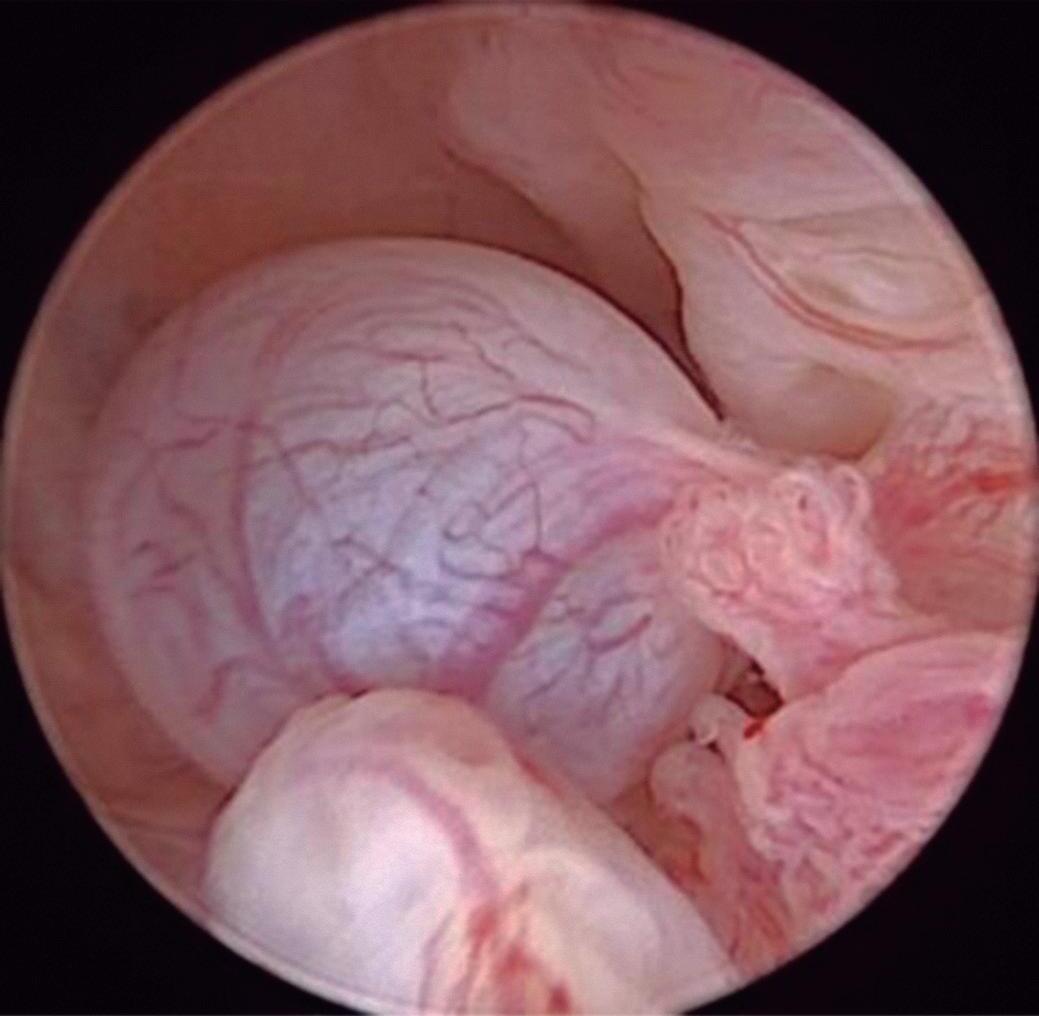

Endométrio Secretor

Apresenta-se rosa-claro ou amarelado e brilhante, superfície ondulada, aspecto esponjoso e aveludado no final da fase. Glândulas amplas, perdendo a forma de pontilhado, principalmente no final da fase, devido ao edema. Os vasos tendem a desaparecer da superfície. Diferente da fase proliferativa, em geral não se observa sangramento ao trauma pelo contato do histeroscópio. Na fase pré-menstrual imediata, aparecem fendas hemorrágicas dando aspecto cerebroide, acompanhadas de pontos hemorrágicos na superfície (Fig. 1-19).